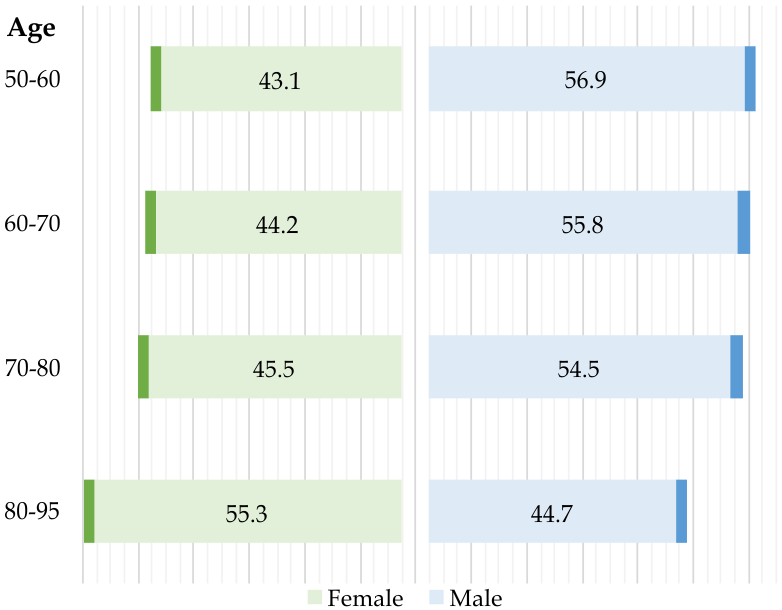

Global health faces a significant burden from colorectal cancer (CRC), the second most commonly diagnosed cancer and third leading cause of cancer-related mortality [1]. Research indicates that approximately 95% of CRC cases originate from colorectal adenomatous polyps [2]. While the overall survival rate for CRC is 63%, early detection and treatment at a localized stage can significantly improve this rate to 91% [2, 3]. Fig. 1(a) summarize the statistics for polyps by age and gender. However, survival drops to 14% when the cancer metastasizes to distant organs. Consequently, early polyp detection and treatment are crucial for CRC prevention and reducing mortality rates. However, the manual detection process is labor-intensive, and variability in clinician expertise can lead to overlooking polyps during colonoscopy.